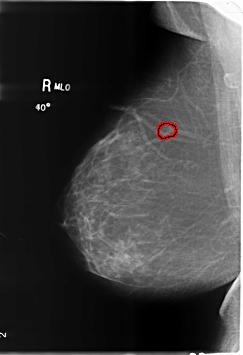

B_3486_1.RIGHT_MLO

RIGHT_MLO LINES 6024 PIXELS_PER_LINE 4120 BITS_PER_PIXEL 12 RESOLUTION 50 OVERLAY

FILE: B_3486_1.RIGHT_MLO.OVERLAY

TOTAL_ABNORMALITIES 1

ABNORMALITY 1

LESION_TYPE CALCIFICATION TYPE PLEOMORPHIC DISTRIBUTION CLUSTERED

ASSESSMENT 4

SUBTLETY 3

PATHOLOGY BENIGN

TOTAL_OUTLINES 1

BOUNDARY